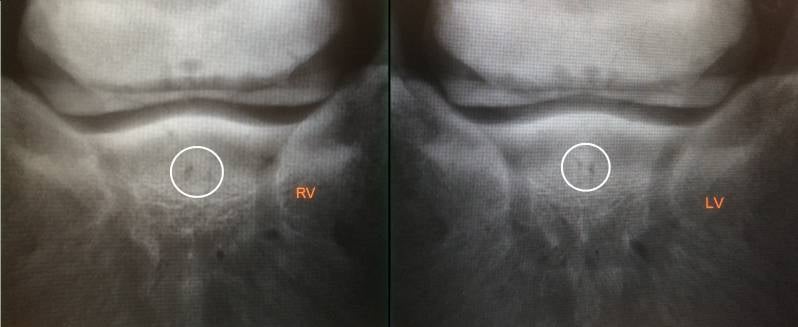

Het hoefbeen, kroonbeen en de diepe buigpees glijden over de achtervlakte van het straalbeen. Tussen de diepe buigpees en het straalbeen bevindt zich ook nog een slijmbeurs. Ligamenten die het straalbeen met de beenderen van de ondervoer verbinden hoort er ook bij.

Met hoefkatrolontsteking word er gezegd dat er een aandoening van de benige en weke delen van het hoefkatrolgebied. Hoefkatrol ontstaat door een overbelasting van het hoefkatrol apparaat. Het ontstaan er van: